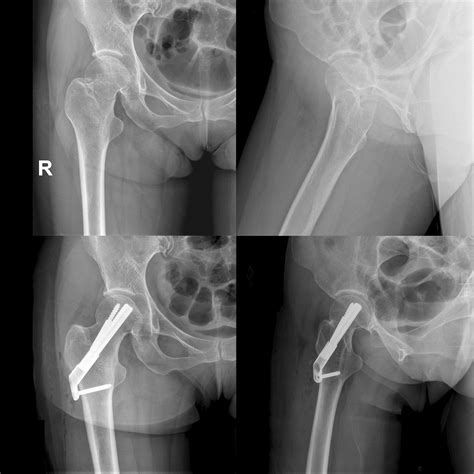

• X-Rays: Standard X-rays to visualize the fracture and determine the extent of bone displacement.

Surgical Treatment

• Open Reduction and Internal Fixation (ORIF): A procedure where the bone is surgically realigned and held in place with plates, screws, or rods.